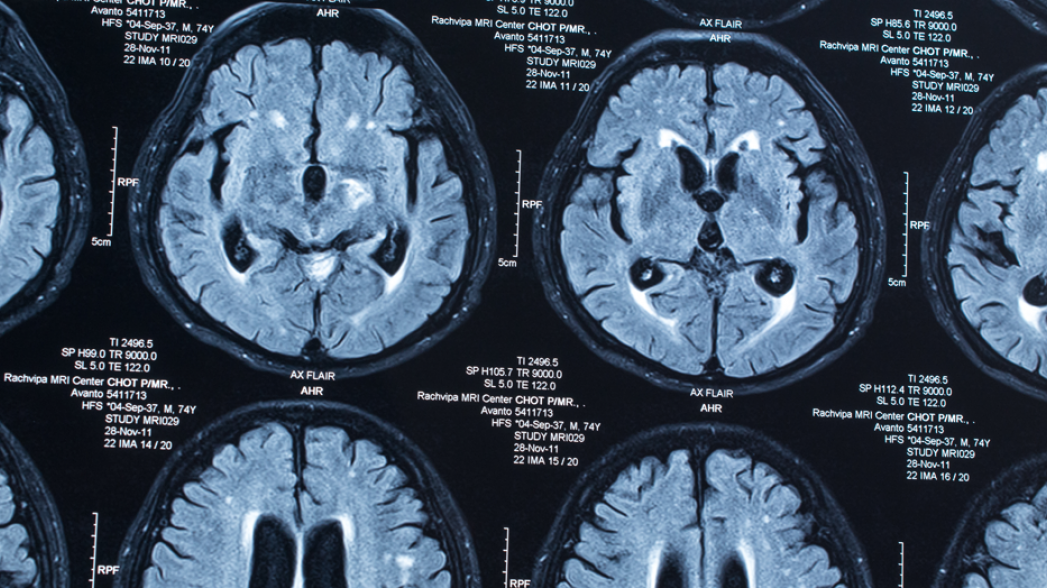

AI ставит диагноз по КТ-скану менее, чем за 2 секунды

Исследователи из Школы медицины Икана Медицинского центра Маунт-Синай разработали решение, позволяющее идентифицировать инсульт, кровоизлияние, гидроцефалию и другие неврологические проблемы за 1.2 секунд. В решении для анализа скана компьютерной томографии (КТ) используются алгоритмы искусственного интеллекта (artificial intelligence, AI). Опубликованное в журнале Natural Medicine исследование, впервые продемонстрировало непосредственное клиническое использование AI для обнаружения широкого ряда неврологических заболеваний.